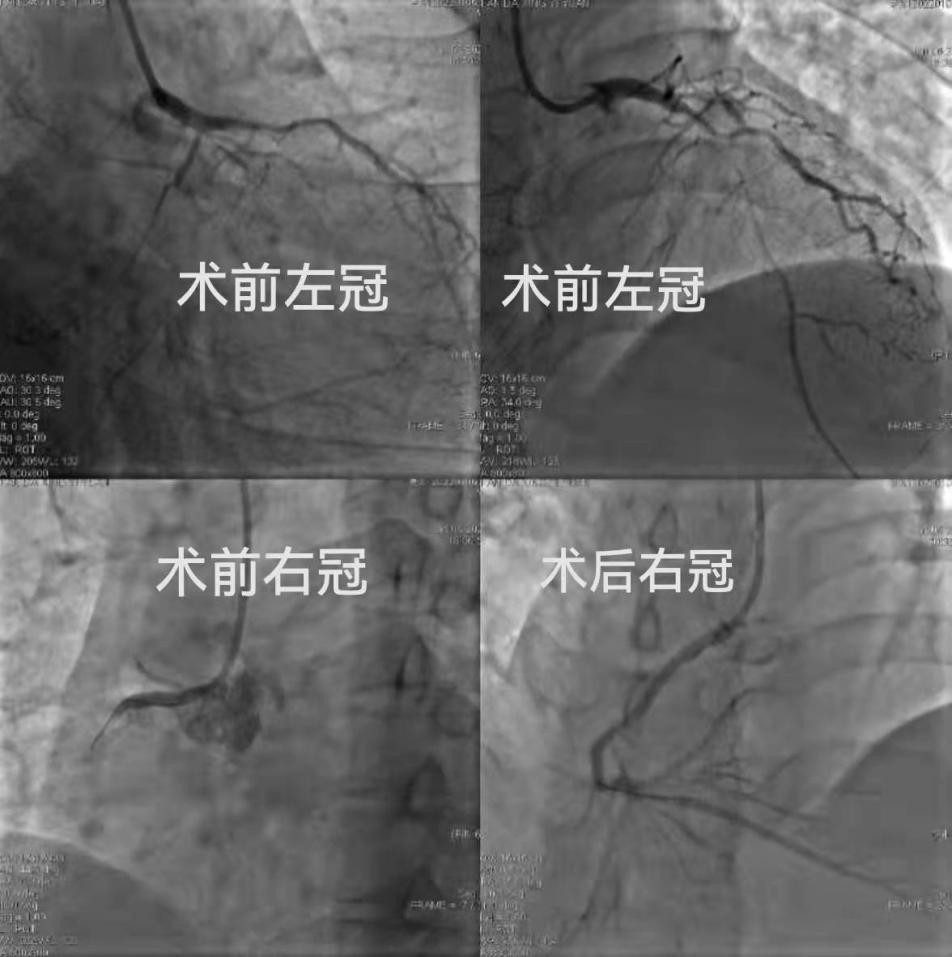

经冠状动脉造影检查,右冠状动脉1段(近段)闭塞、前降支7段(中段)闭塞、回旋支12段(中段)闭塞。病情危急!

安装临时(心脏)起搏导管保护,成功打通血管后,闭塞远端为弥漫性病变。球囊扩张后植入支架2枚。